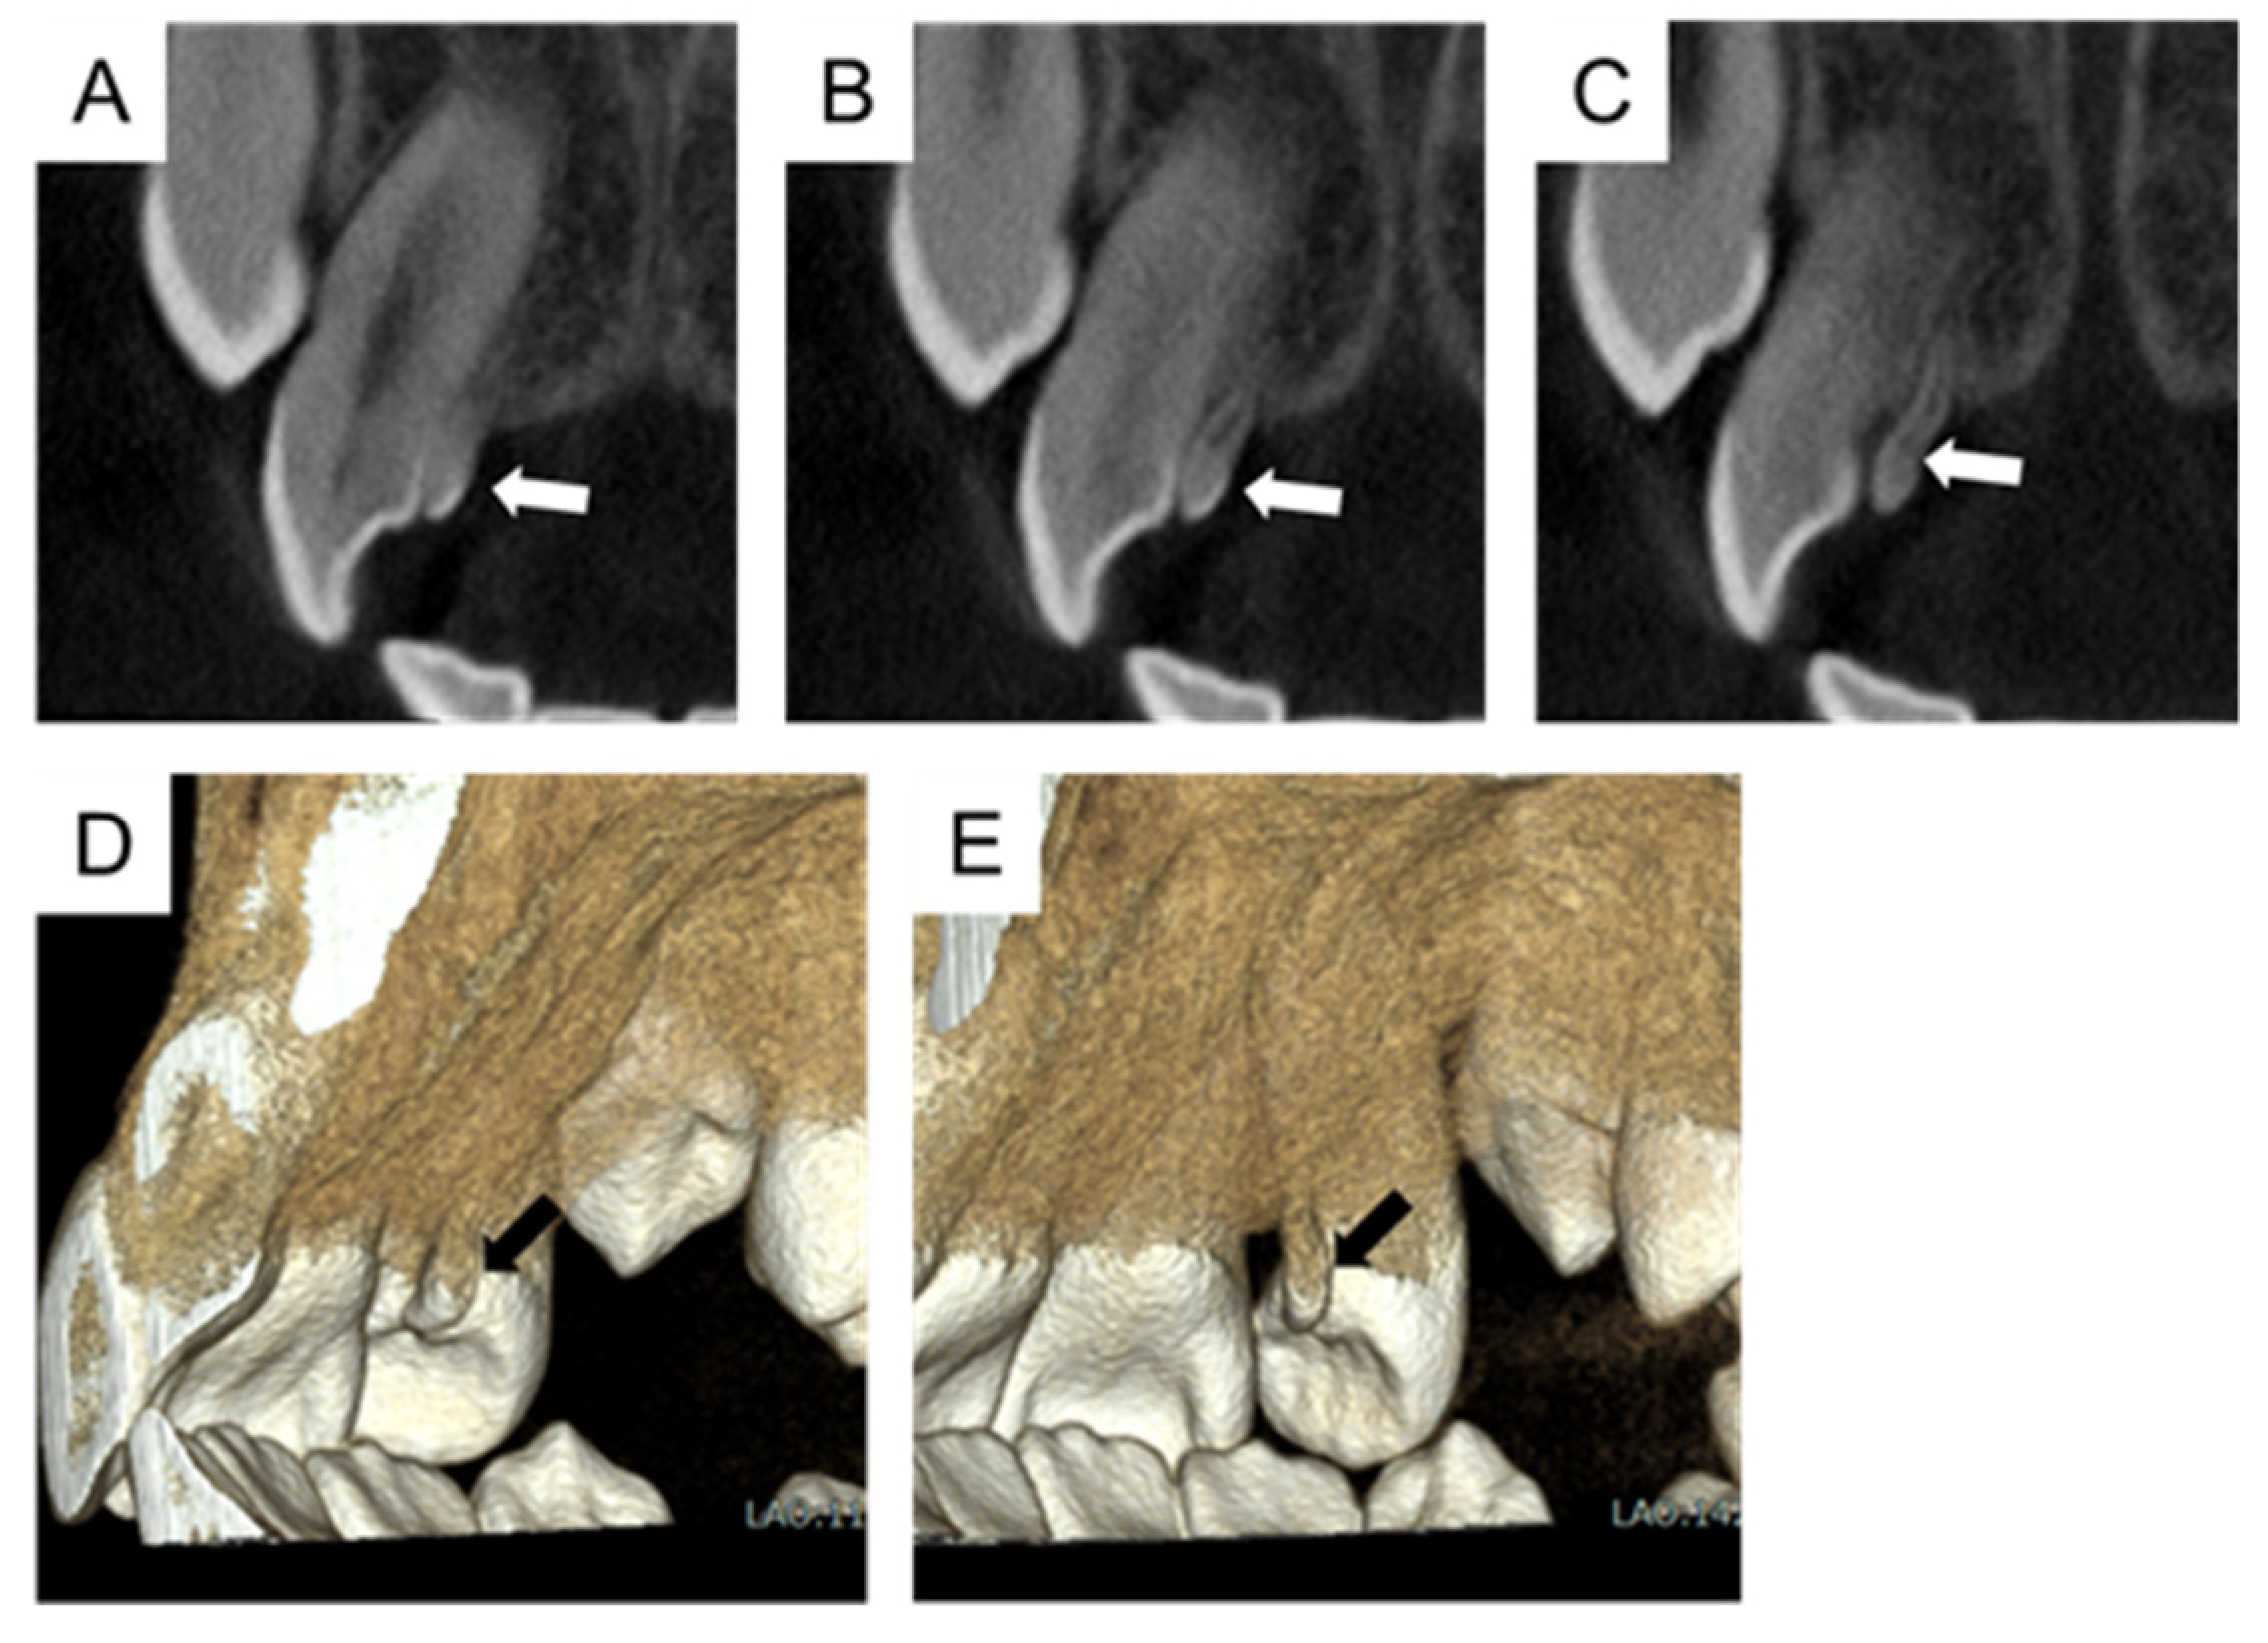

2. Case Presentation

5.2. The Present Case